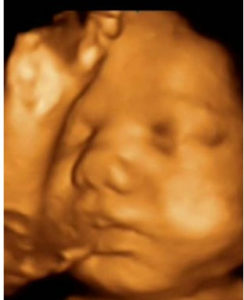

ecokEl Centro de Ginecología y Diagnóstico Prenatal Iquique, cuenta con profesionales de excelencia, tecnología y técnicas de diagnóstico de última generación.